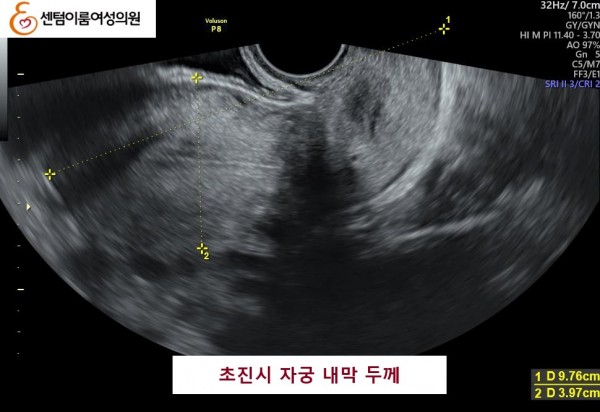

2024.12월 본원 내원 전 타병원에서 다수의 시술 경험이 있으셨습니다.

40세 이상 고령 연령은 염색체 비정상 난자 비율이 높아 고난도 난임의 대표적인 사례입니다.

꾸준한 식생활 개선과 약물 치료를 받으시고 임신에 성공 하셨습니다.